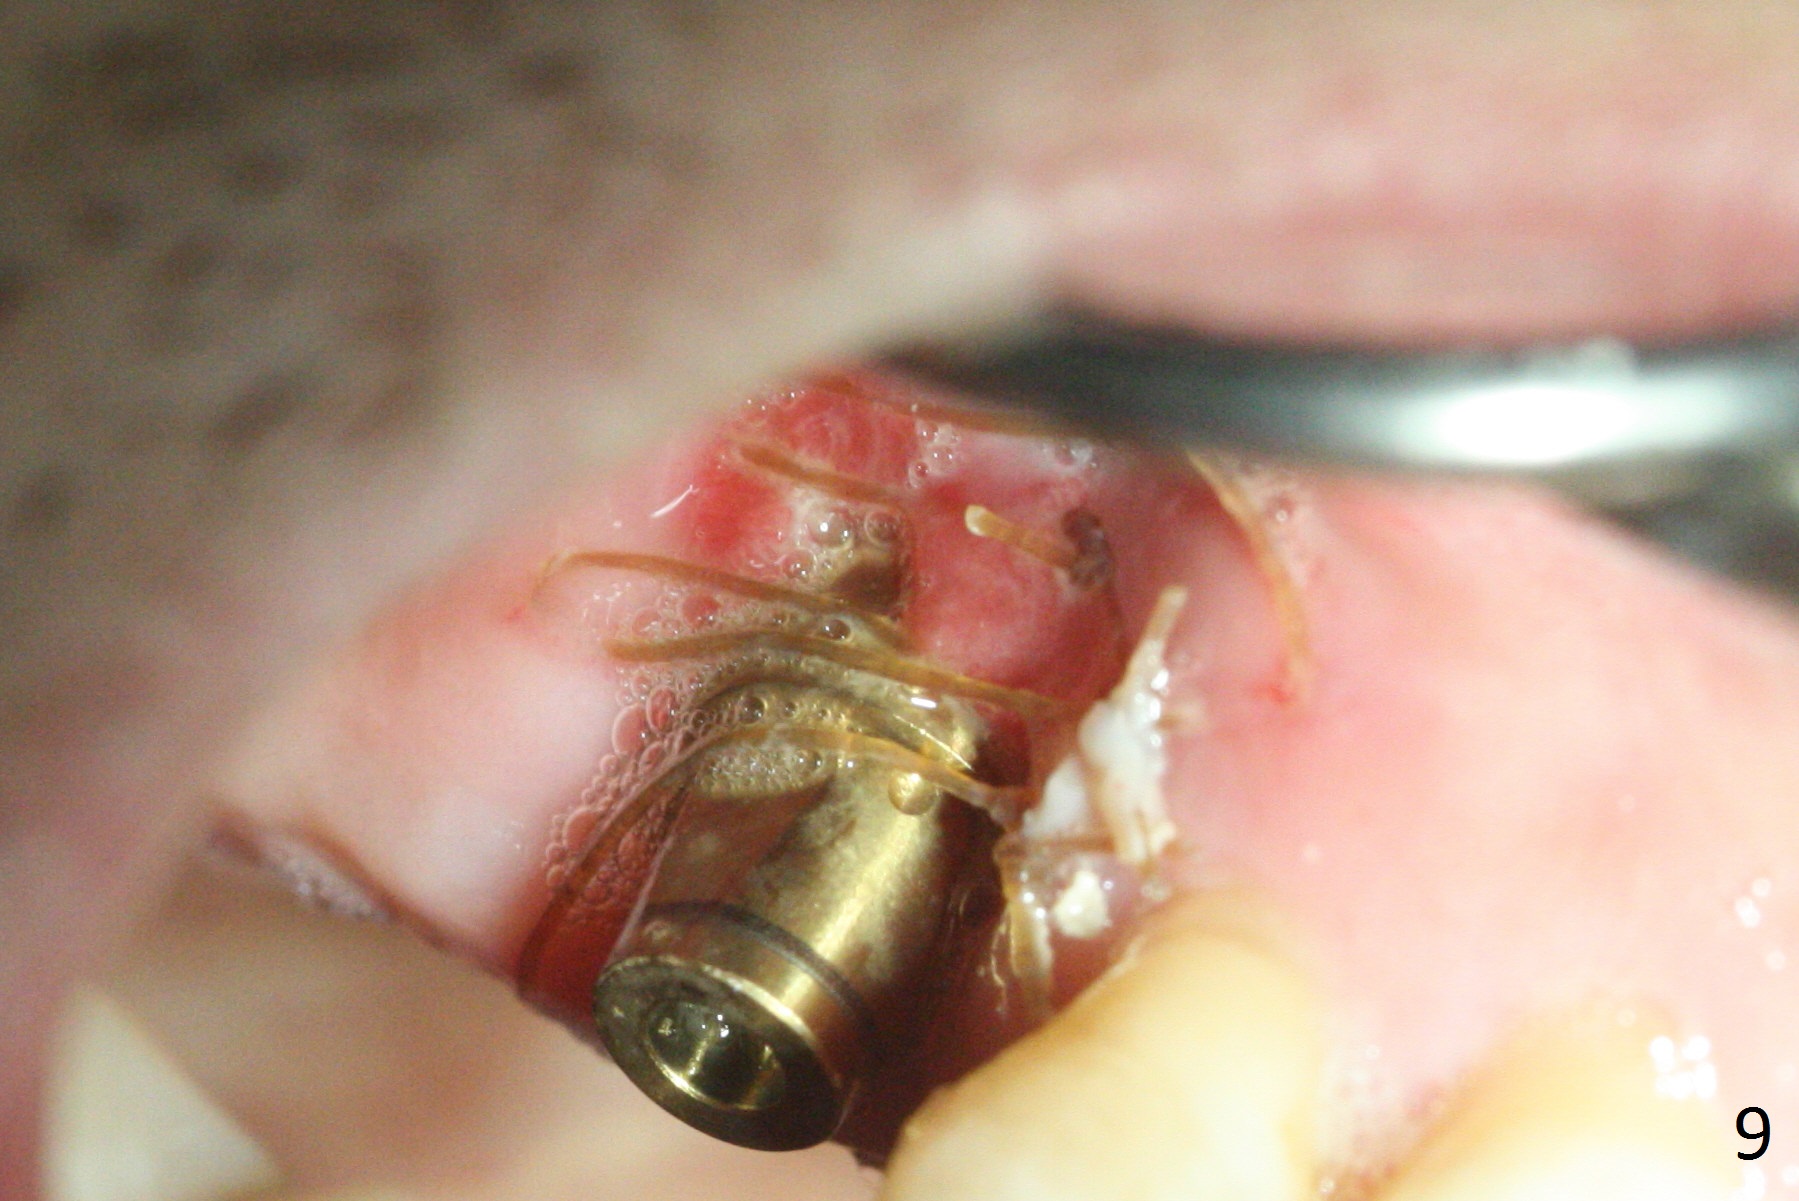

The distopalatal portion of the periodontal dressing dislodges 10 days postop. It appears after removal of the remaining dressing that PRF membranes has dissolved, while the remaining buccal and septal gingiva is healing (Fig.9). The wound leaves open for secondary healing.